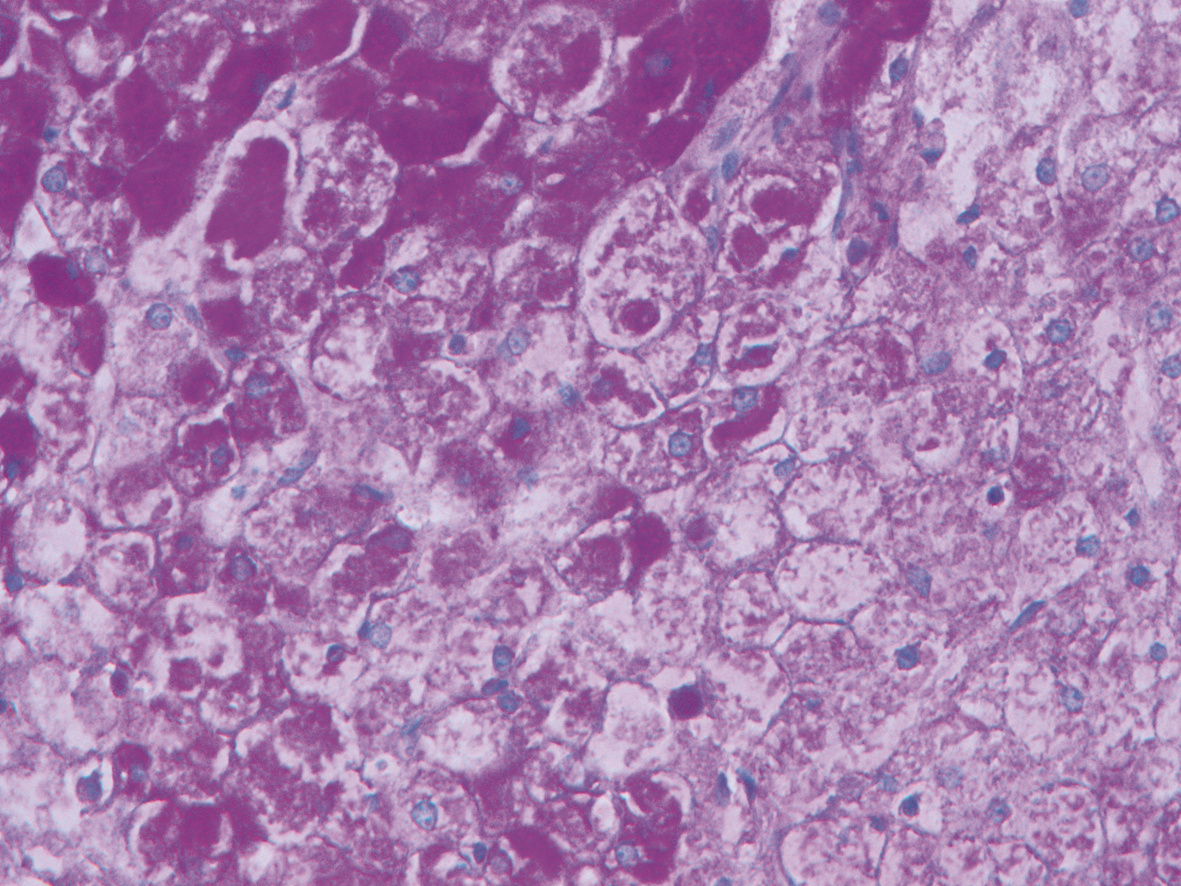

10例儿童肝糖原累积病临床及病理学分析

赵素贤, 刘世恒, 李文聪, 韩芳, 刘树红, 张庆山, 任伟光, 孔令波, 付娜, 王荣琦, 孔丽, 南月敏, 赵景民

2022, 38(8): 1839-1842. DOI: 10.3969/j.issn.1001-5256.2022.08.022

摘要(1407) HTML (512) PDF (2394KB)(109)

摘要:

目的  探讨儿童糖原累积病(GSD)的临床及病理学特点。  方法  选择2002年1月—2022年1月河北医科大学第三医院及解放军第五医学中心经病史、肝脏生化及肝活组织检查确诊的GSD 10例,对比分析人群特征、临床表现、生化指标、肝组织病理学特点。  结果  10例患儿发育迟缓,矮小,均表现为肝功能异常,轻度乏力、纳差、尿黄、眼黄,4例患者肝脾肿大。6例患者有低血糖的临床表现;1例患儿双侧腓肠肌肥大,Gower征阳性。2例患儿巨细胞病毒IgG阳性。肝组织病理学表现肝细胞弥漫性肿大,胞浆空淡,核小居中似植物细胞状,伴或不伴纤维组织增生。  结论  GSD患者多数有发育迟缓、转氨酶异常,肝组织病理检查有其特异性病理特征。